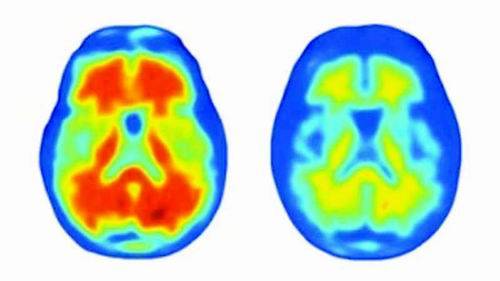

患有阿尔茨海默病和其他老年痴呆症的患者常出现“日落症候”,即在白天结束时突发性暴躁。塞珀认为,控制生物钟有可能会让患者更加平和。